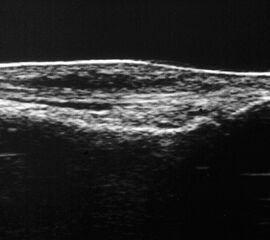

Referenzstruktur: Direkt unter der Haut und der dünnen Subkutis liegt echogen und straff parallel die Achillessehne mit ihrem echogenen Peritendineum (Abb. 53), Tuber calcanei.

Befunde: Da die Sehne zumeist nicht glatt, sondern bündelförmig reißt, stellen sich auch in der Sonographie anders als bei den Peroneal- und Flexorensehnen keine spargelspitzenähnlichen Rissenden dar. Echogene Rissränder, umgeben von echoarmem Hämatom sind beweisend für eine Ruptur. Risse der Achillessehne können auch nur einen Teil des Sehnenquerschnitts betreffen. Daher ist die Untersuchung verschiedener TS bedeutsam (Abb. 54 bis 56). Unter Kontrolle am Monitor kann die Diagnose in maximaler Dorsalextension klarer gestellt werden (Abb. 57).